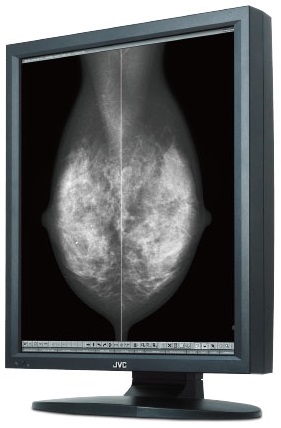

JVC MS55i2 plus

5 MP 21,3” monochromatyczny monitor LCD z podświetleniem LED

MS55i2 plus to nowo opracowany przez JVC (dawniej TOTOKU) monitor monochromatyczny o przekątnej 21,3", rozdzielczości 5MP i bardzo wysokiej maksymalnej jasności wynoszącej aż 2000 cd/m2. Jest on przeznaczony do diagnostyki opisowej zdjęć mammograficznych. Monitor ten może być skalibrowany do pracy z jasnością do 1000 cd/m2, dzięki czemu nadaje się doskonale do wyświetlania zdjęć z tomosyntezy, zwiększając zauważalnie widoczność mikrozwapnień i guzków.